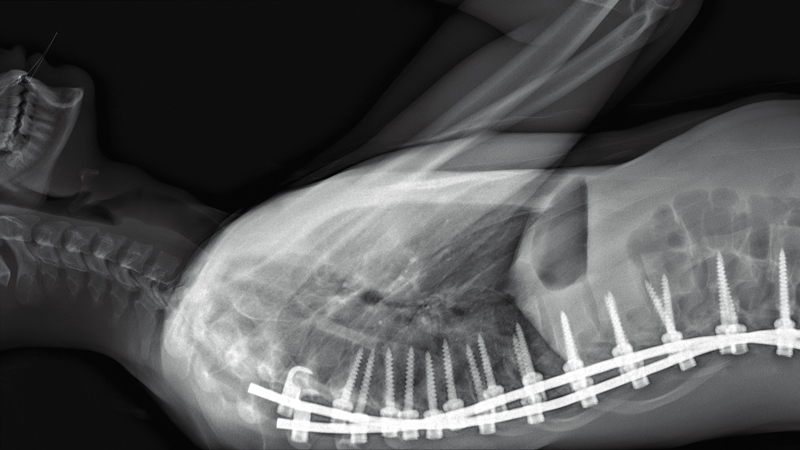

H・P・ラヴクラフト作品すら彷彿させる漁船のカオスを映し出した『リヴァイアサン』を手掛けたあのコンビだけに、今回も本編には一切のナレーションやテロップなし。GoProを最先端医療カメラに持ち替え、頭部にはじまり眼球、消化器官から子宮・胎盤、そして胸椎までをパックリゴリゴリに映し出す。言葉を選ばずに言えば、めちゃくちゃグロテスクな映像の連続である。